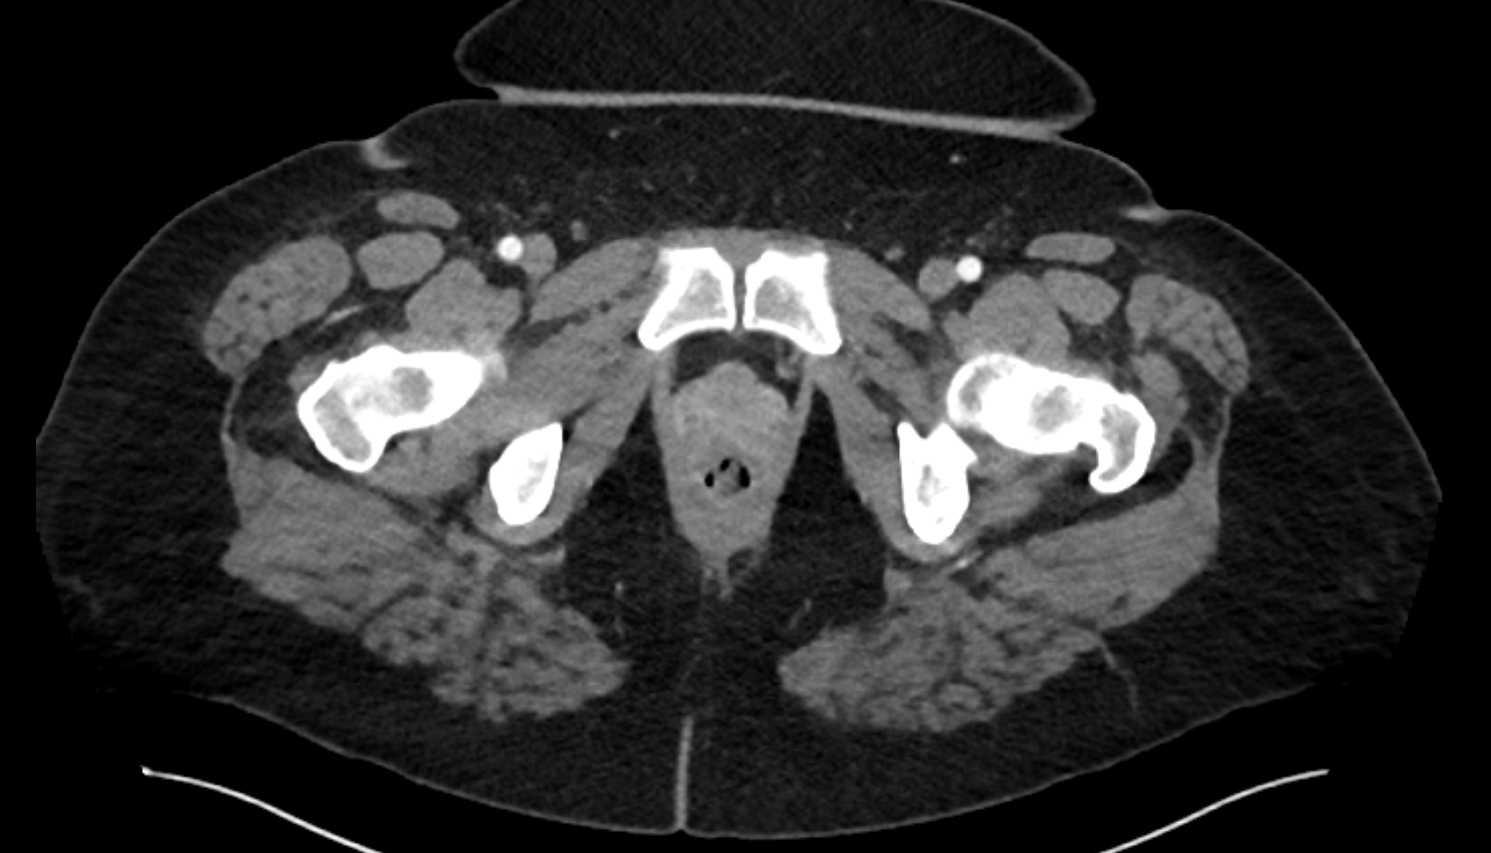

- Acetabular margin (Acetabular rim)

- Acetabulum

- Head of femur

- Neck of femur

- Hip joint